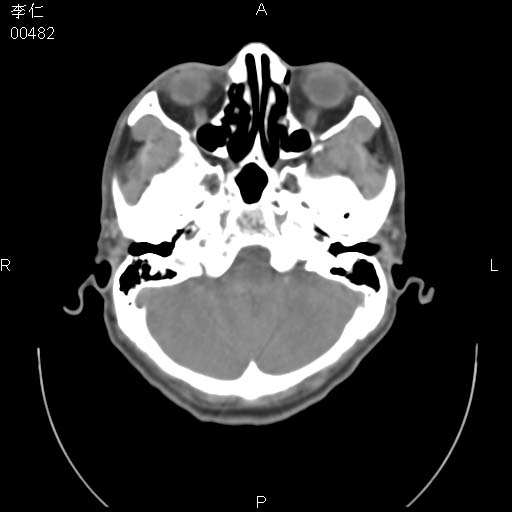

患者男,45岁。于二月前发现左眼稍肿,去看眼科,查肾功(—),来查ct,我看到的是左侧上眼睑内低密度影,ct值是-600到-700hu。

是一个副鼻窦的正常变异,脂肪瘤的密度不可能这么低,-600到-700.

只是空气而已,属正常ct表现。

正常表现,眼睑与结膜zhi间的空气

正常,为结膜囊内气体。

左侧眼球壁光滑,未见异常密度灶,眶内结构清晰,眼内肌、视神经均正常。所见低密度灶,本人考虑:1、五官科翻上睑造成;2、炎症(产气细菌感染)。